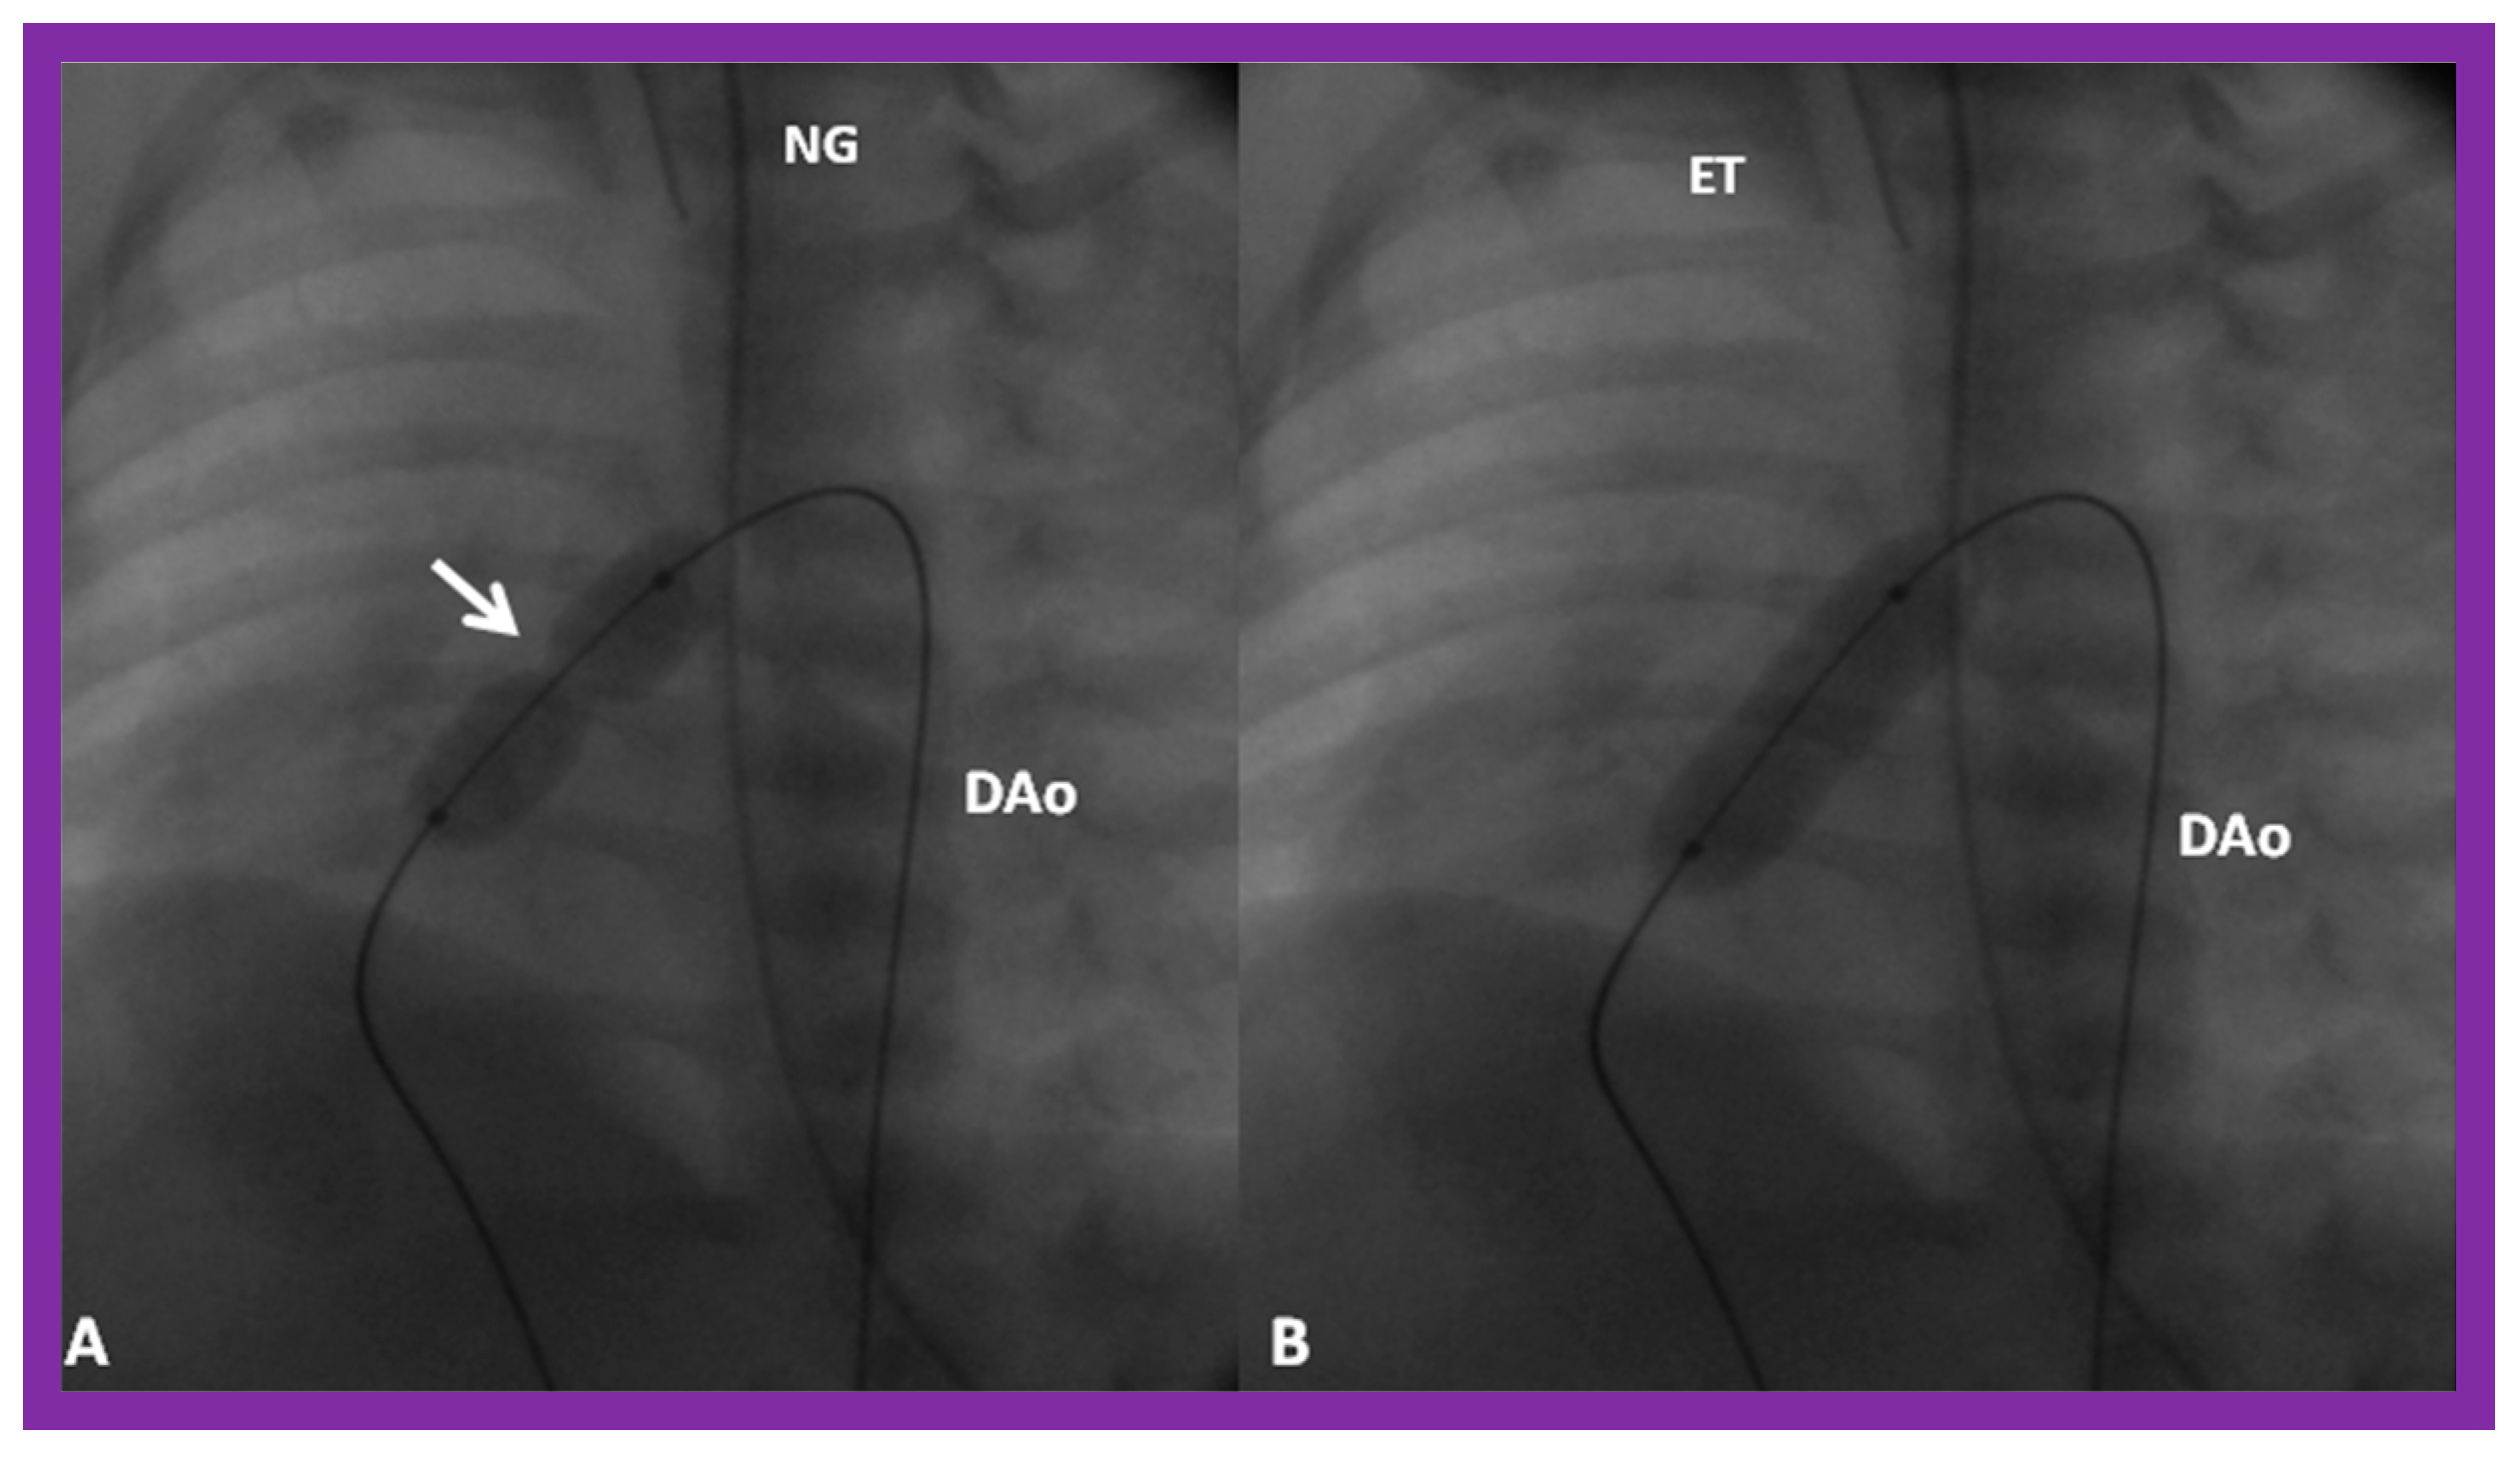

Pulmonary Stenosis in the Fetus

Aortic Stenosis in the Fetus